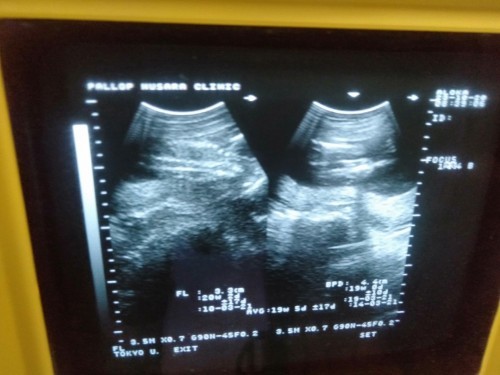

ผู้หญิงรึผู้ชาย

มีแม่ๆคนใหนดูออกมั้งคะว่าหญิงรึชาย👶

มองไม่ออกเลยจ้า หมอว่าไงคะ

กำลังตั้งครรภ์